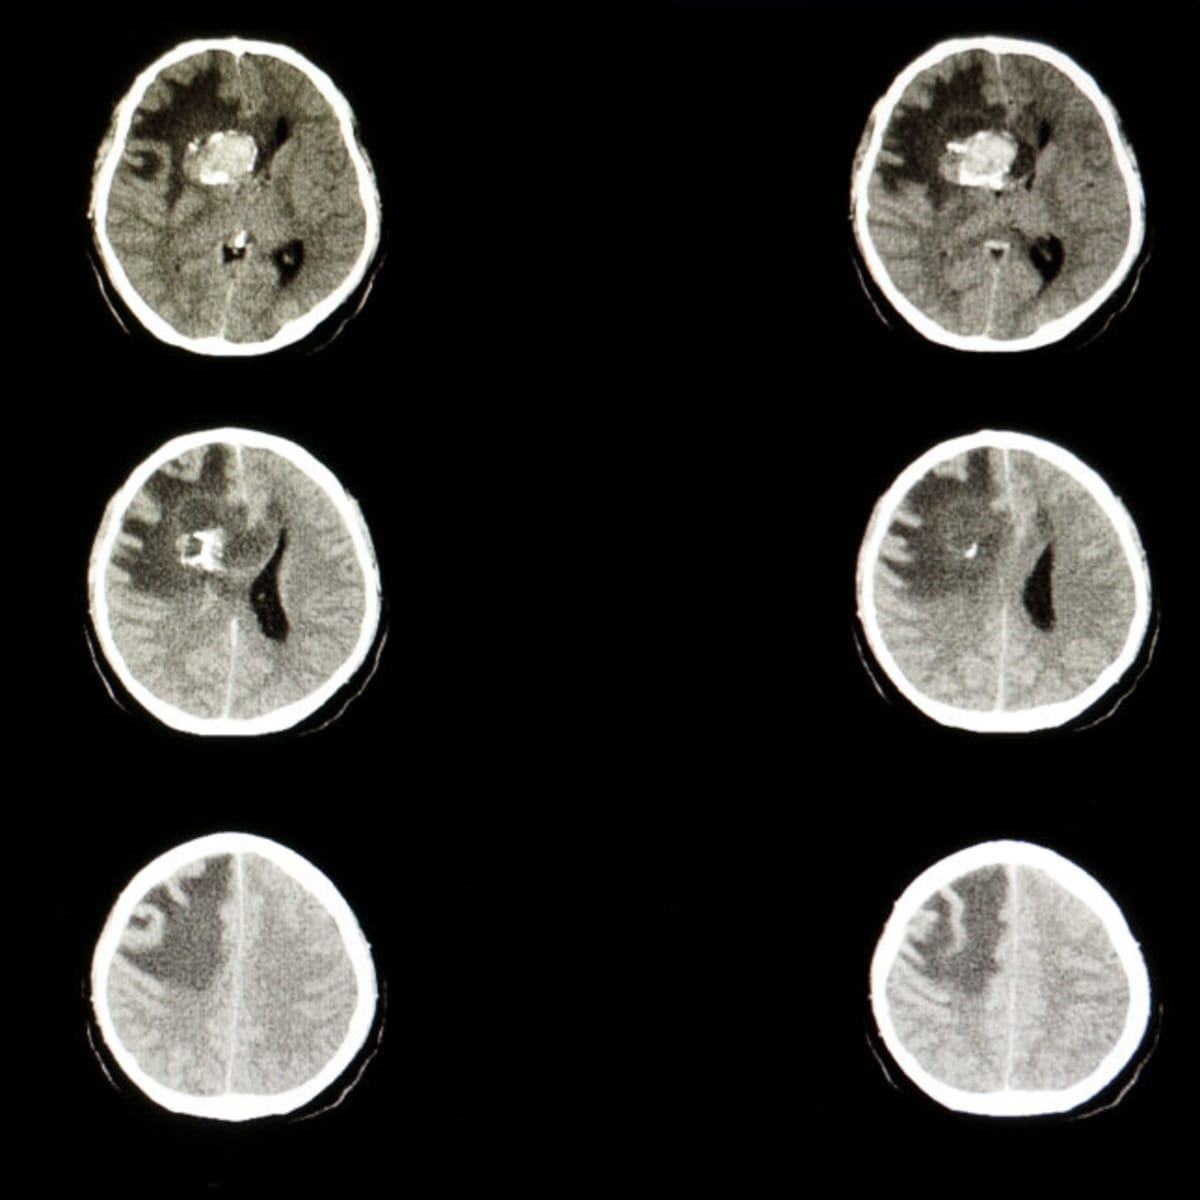

The Bay Area biotech company makes Ojemda, a drug approved in 2024 to treat pediatric low-grade glioma. This is the most common type of brain cancer in children.

Pediatric low-grade glioma affects thousands of children every year. Before Ojemda's approval, treatment options were limited and often came with harsh side effects that could impact a child's development.